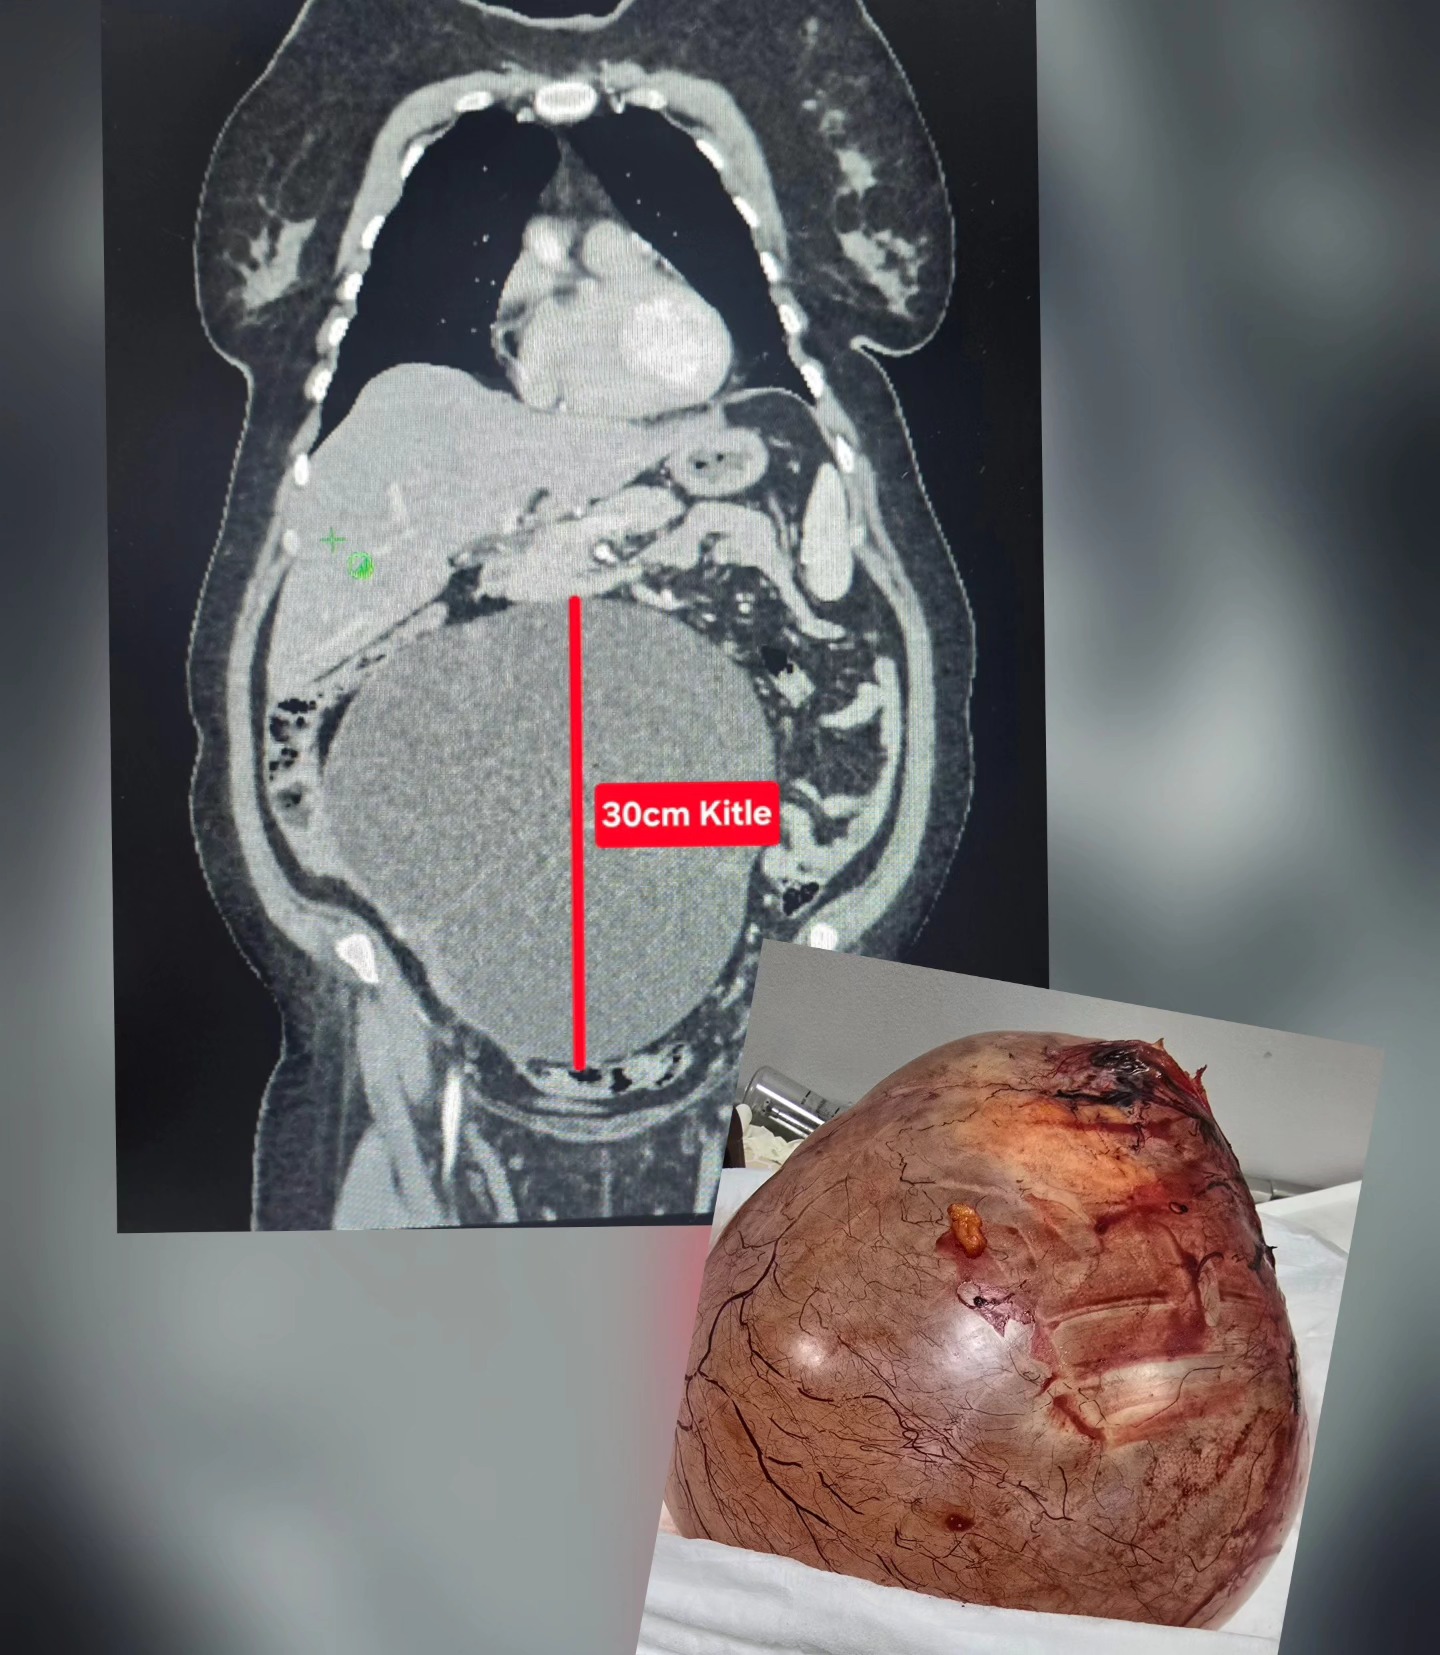

Uşak’ta şiddetli ağrı, kabızlık ve şişlik şikayeti bulunan bir vatandaş, Uşak Özel Öztan Hastanesi’ne başvurdu ve burada yapılan kontrollerde karın bölgesinde büyüyen ve 30 santimetreye ulaşan dev bir kitle tespit edildi. Özel Öztan Hastanesi’ndeki Kadın Hastalıkları ve Doğum ve Genel Cerrahi ekibi, tarafından yapılan bir operasyonla dev kitle çıkarıldı ve hasta yeniden sağlığına kavuştu.

Genel Cerrah Op. Dr. Aydın Tükenmez, yapılan operasyonun detayları hakkında bilgiler verdi. Yaklaşık 3 saat süren ameliyatta kitle eksizyonu, apendektomi, omentektomi ve TAH-BSO olarak adlandırılan operasyon uygulandı. Uşak Özel Öztan Hastanesi Yönetimi, operasyonda görev alan ve özveriyle çalışan tüm sağlık personeline teşekkür ederken, bu tür şikayetleri olan vatandaşların en yakın sağlık kurumuna başvurarak kapsamlı bir tahlil ve tetkik yaptırması ve ilgili uzmanlardan destek alması istendi.